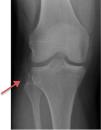

Se realizaron radiografías de rodilla evidenciando una fractura de Segond (fig. 1).